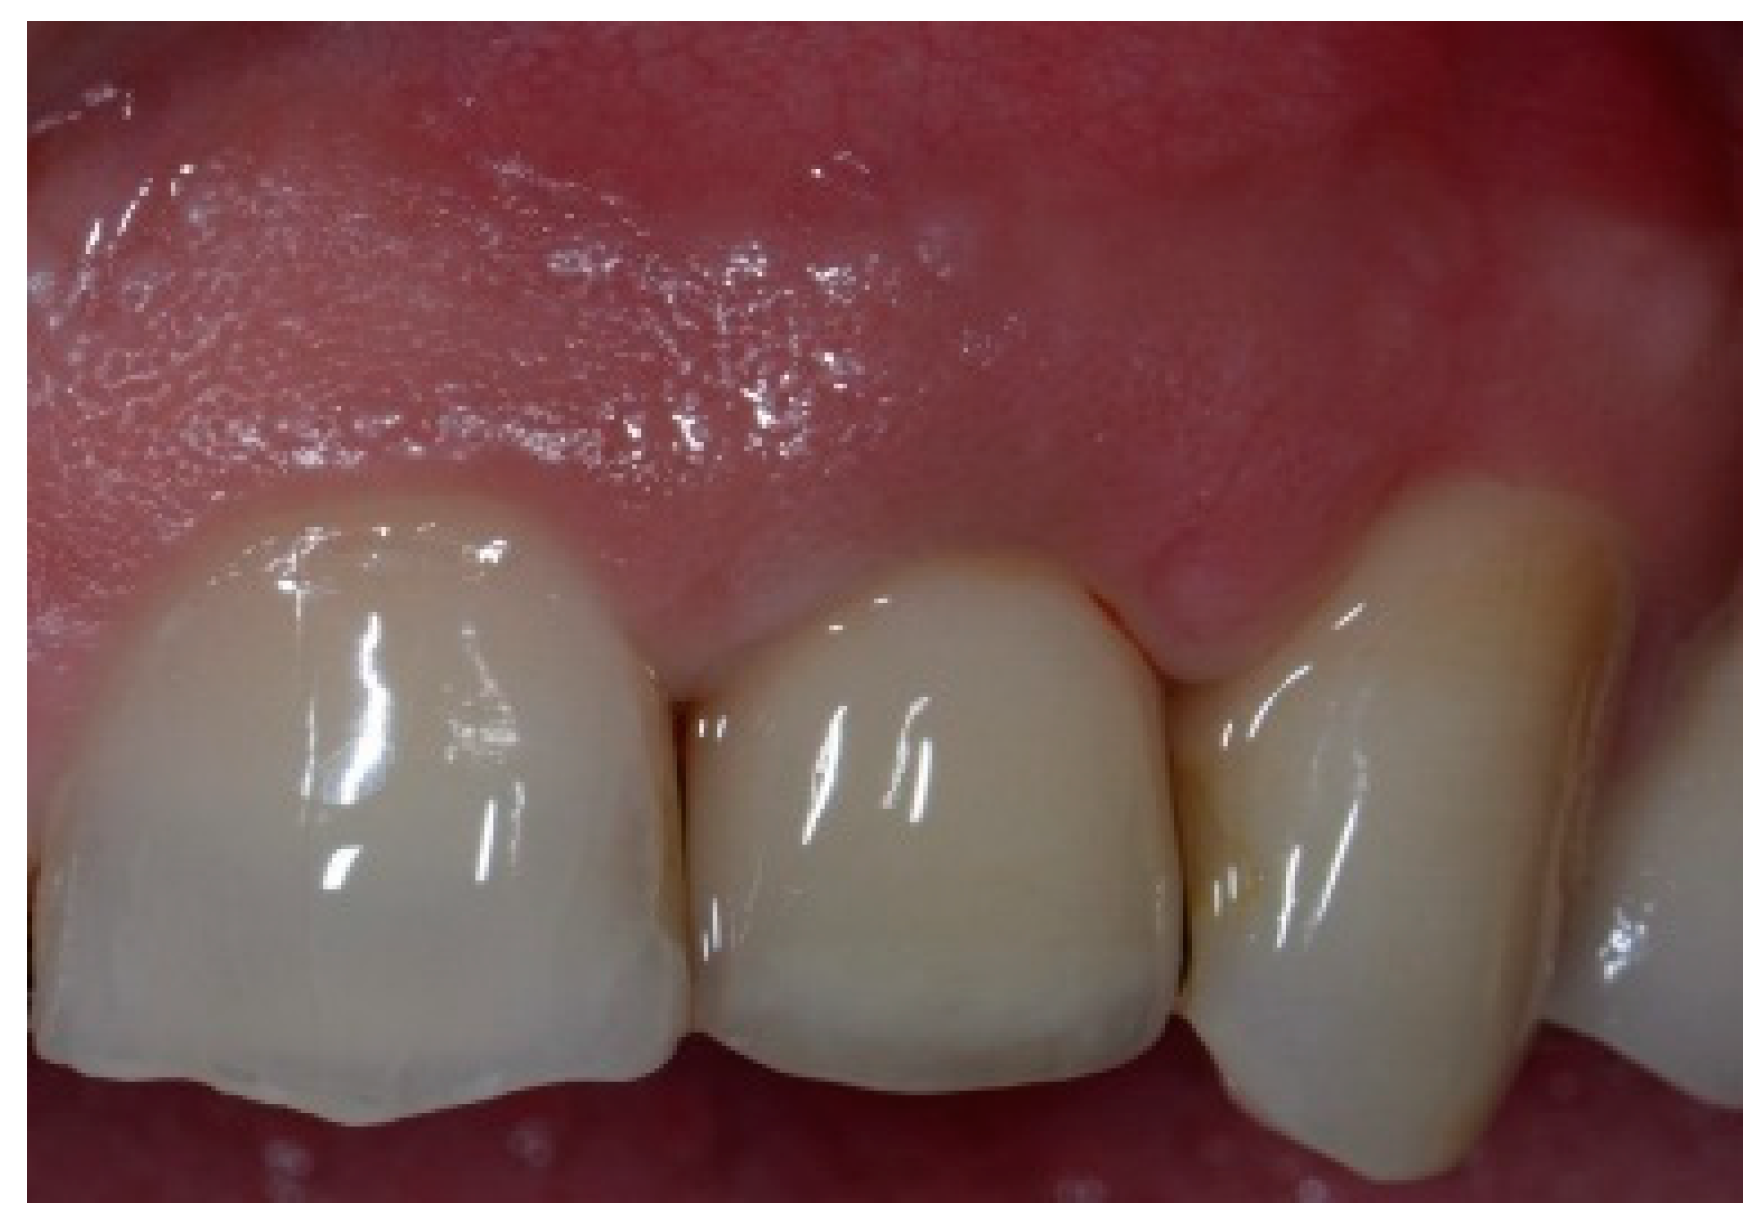

Figure 6.

Clinical view of the implant site before final restoration.

Following a 6-month healing period (Figure 6), definitive prosthetic rehabilitation was carried out using zirconia CAD CAM abutments (Straumann, Andover, MA 01810, USA). The ceramic zirconia crowns of teeth 8 and 9 were placed (Figure 7). At the two-year follow-up examination for patients #1 and #3 and three-year for patients #2 and #4, the implants were fully osseointegrated, presenting satisfactory functional and esthetic conditions without clinical or radiographic signs of any pathology.